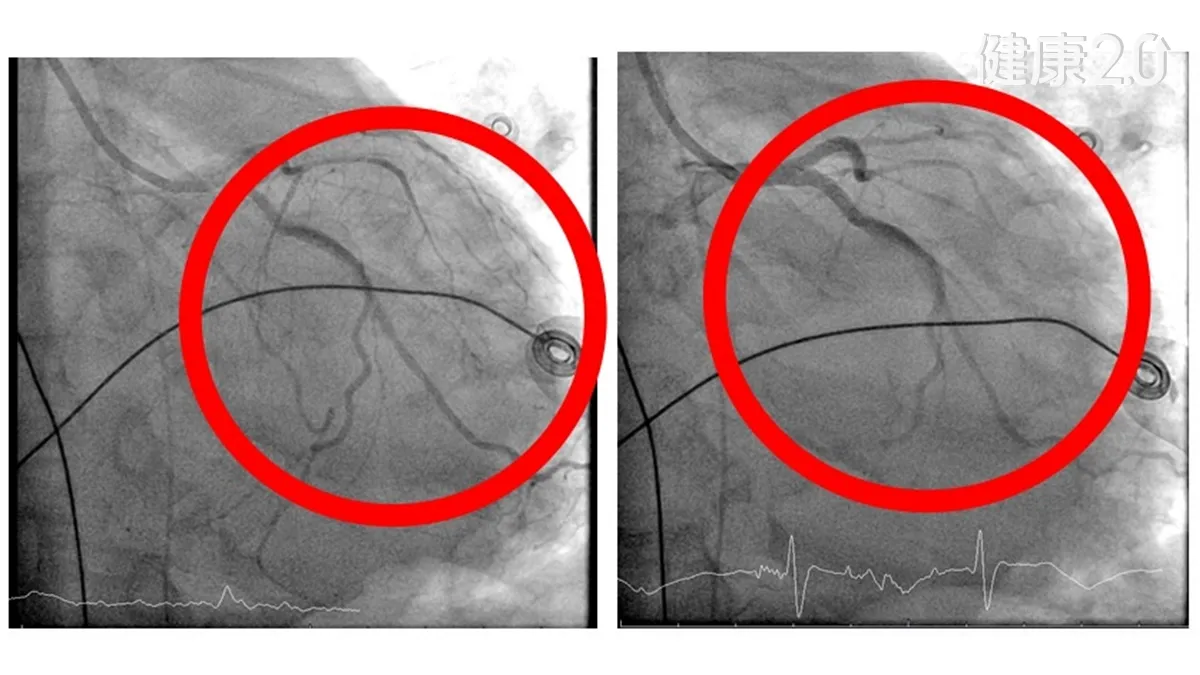

放完支架當晚竟二度心肌梗塞!60歲男失去脈搏險死「1措施」救了他

...受心導管介入手術,不料術中突發少見的右冠狀動脈急性閉塞,引發心因性休克,心跳過慢,呼吸衰竭須插管。彰化醫院穩定其生命徵象後轉送台中...